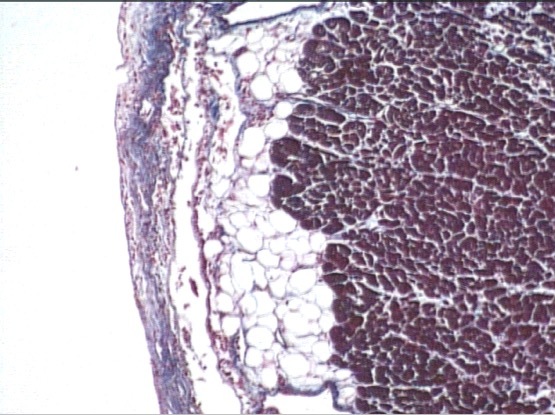

lymph node

cotex

pericortex

medulla

outer cortex lymph node (B-cells)

paratrabecular sinus

subcapsular sinus

(lymphatic fluid)

trabeculae

CT capsule

cortex

primary nodule

secondary nodule

subcapsular & paratrabecular sinus